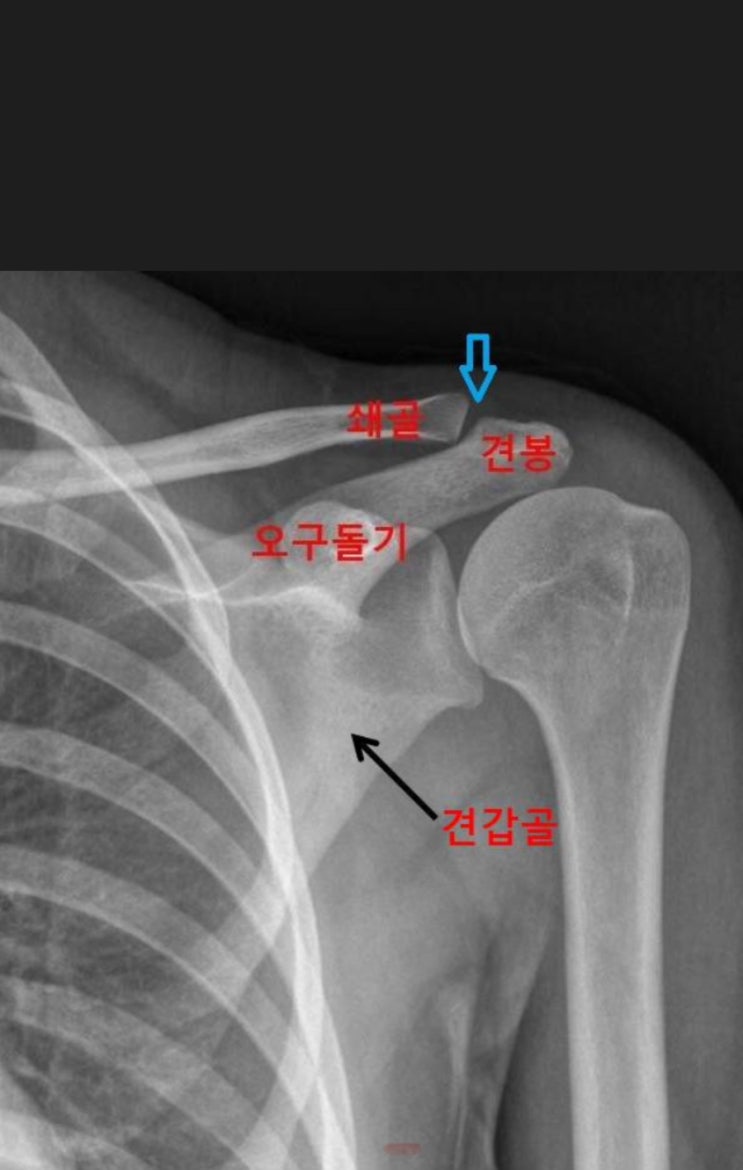

탁구-오른손 무리한 탁구로 부상, 왼손 탁구로 전향에 어려움-왼손탁구로 전향-견봉쇄골인대 관절염

2024.06.14 작년 2023.11월 손발 맞는 형님과 생활체육센터를 월화수 같이 등록해 09시 만나 한시간 둘이 ...